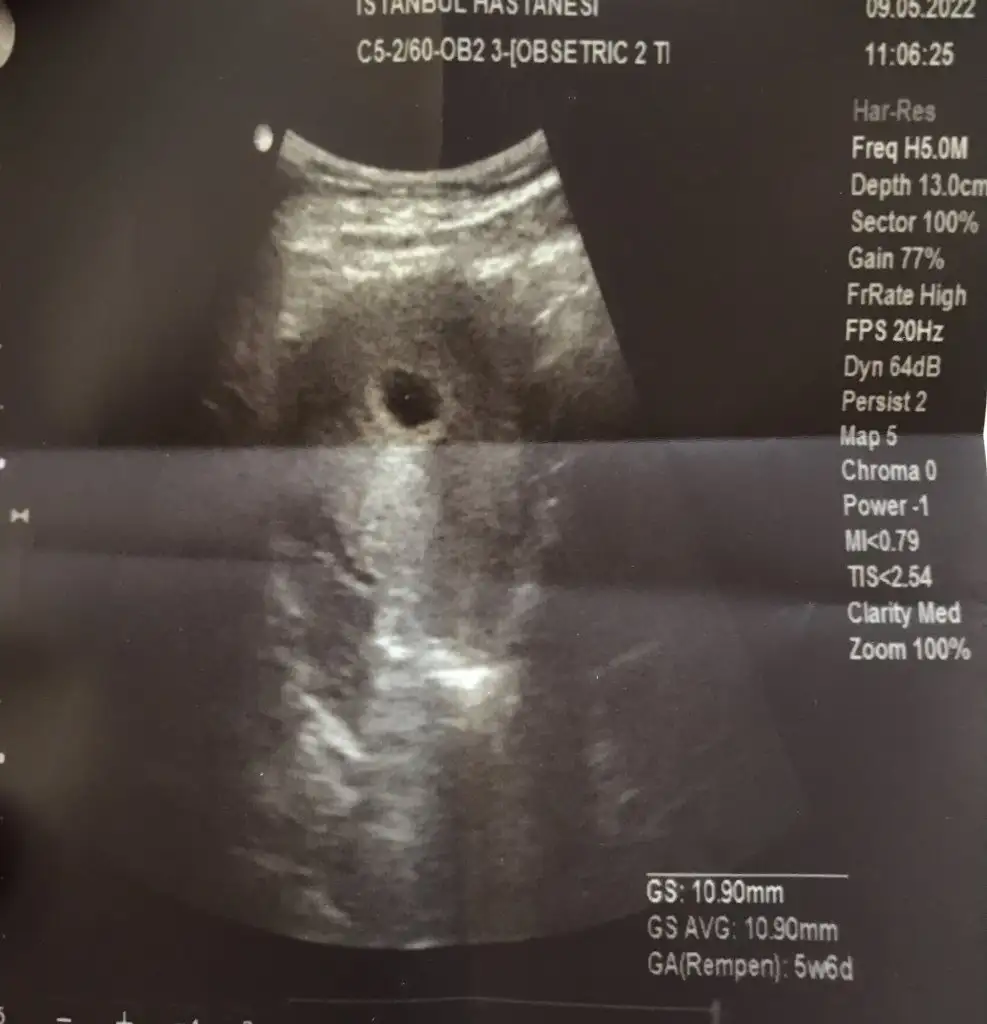

5+6 da öğrendim kese gözüktü sadece haftaya gel hem kalp atışını hem de bebeği görürüz dedi. 6+1 oldum şuan 5+6 kese görüntüsü böyle boş görünüyor tedirgin oluyorum

Benim 10.90 mm canım 5+6 seninkisiyle arasında 1 hafta var İnan 1 günde neler değişiyor küçük değil bence normal henüz daha çok erken seninki